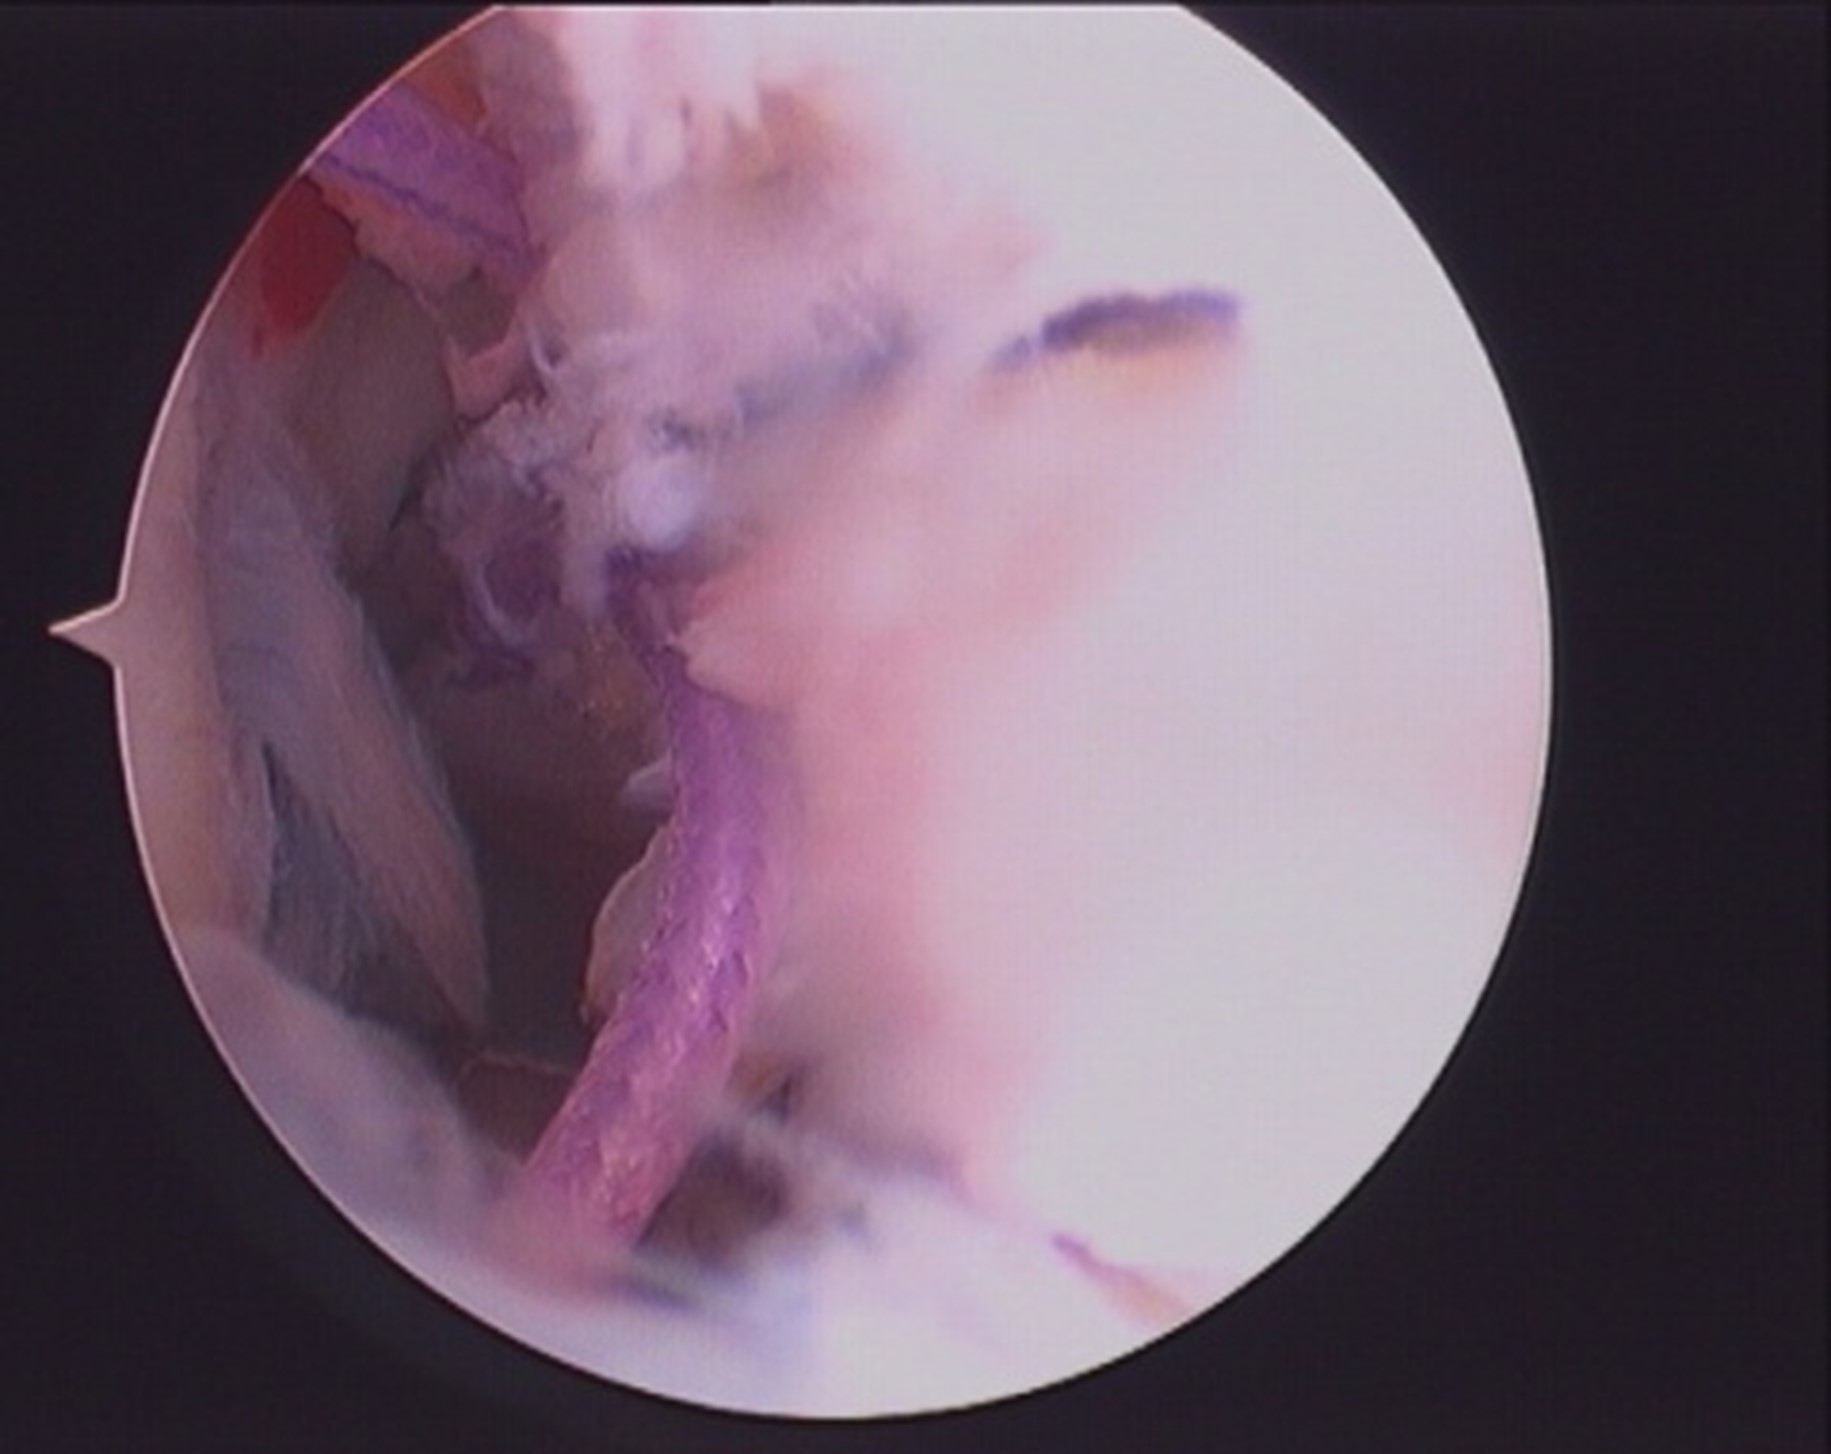

- Both ends of the suture loop are delivered posteriorly through inferior PM portal and sliding knot is passed and sitted over the osseo-ligamentous fragment.fig 3, 4.

- Suture ends are delivered anteriorly through the tunnel and pulled to reduce the fragment and tied over the suture washer with knee in extension.